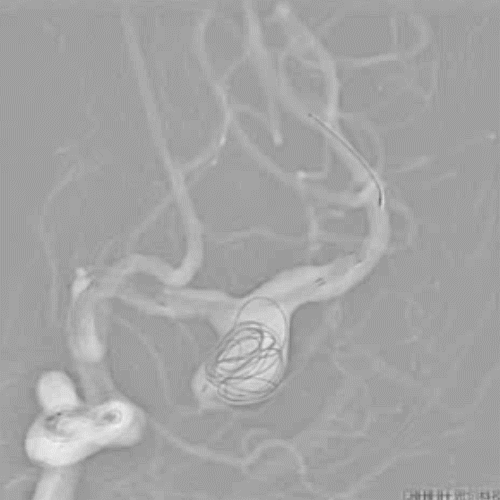

4、经Marksman™ 微导管输送Pipeline™ Flex 血流导向密网支架 375-35,准确输送到位后,开始释放Pipeline™ Flex 血流导向密网支架。

5、使用推拉结合方法继续缓慢释放Pipeline™ Flex 血流导向密网支架,确保支架远端和中动脉贴壁良好,再向前推挤支架使可见中间导管自动向近段移位,间断予以释放中间导管张力后,再使用前诉方法释放支架,确保支架与载瘤动脉良好贴壁。

6、支架释放至覆盖瘤颈约1/2处,继续经Echelon™ 10微导管填入多枚弹簧圈,给予支架充足的支撑力后,继续使用推拉技术释放支架,最后支架近段着陆于左侧大脑中动脉M1段。

7、动脉瘤内继续填入弹簧圈将动脉瘤致密填塞,正位造影观察大脑中动脉血流通畅。